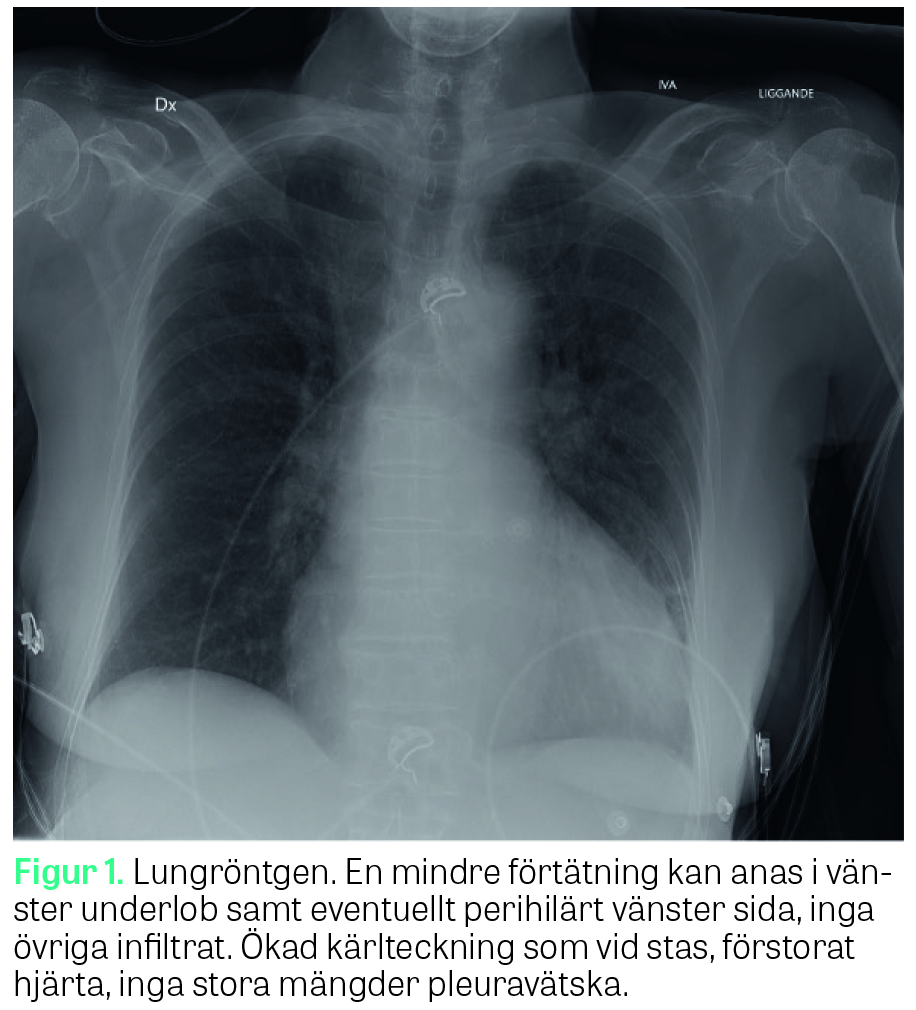

Kort efter ankomst till Iva skedde en allmän drastisk försämring. Patienten blev tilltagande orolig och medvetandepåverkad. Trots högflödesgrimma med FiO2 1,0 visade pulsoximetrin fortsatt dålig kurva, med SpO2 85 procent. Cirkulationen sviktade med fallande blodtryck till 70/40 mmHg och tilltagande takykardi, 140/min. Marmoreringen tilltog mot ljumsknivå liksom på händer och fingrar. Näsan och läpparna blev kraftigt cyanotiska. Utöver pågående vätskebehandling startade man katekolamininfusion med noradrenalin i hög dos. När artärkateter anlades noterades rostfärgat blod, och en artärblodgasanalys bekräftade MetHb 28,3 procent, sjunkande pH 7,1, laktat >17 mmol/l och hypoglykemi 1,0 mmol/l. De venösa ankomstproven visade CRP 305 mg/l, Hb 107 mmol/l, TPK 46 × 109 E/l; APTT 104 s, INR 1,5, kreatinin 508 µmol/l och kraftigt förhöjda transaminaser. Toraxröntgen visade förtätning i vänster underlob och breddökad hjärtskugga (Figur 1).